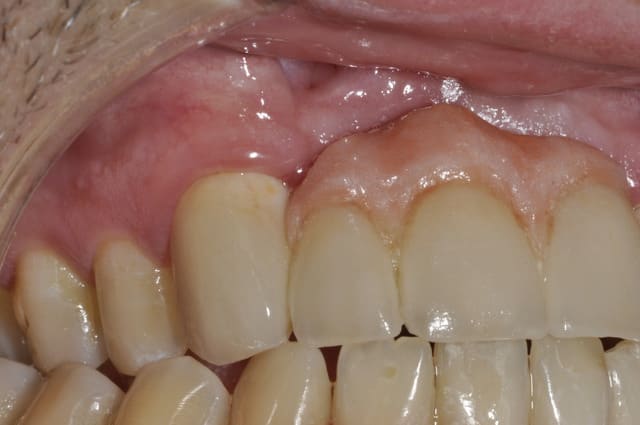

On constate des petites zones inflammatoires au niveau des piliers et une légére perte d'attache sur la 23.

Photo prise juste après le détartrage, mais n'excuse pas tous.

Le fini de la céram semble rugueux ?

Avec sa belle gingivite/paro...le patient aura des ennuis...je pense...